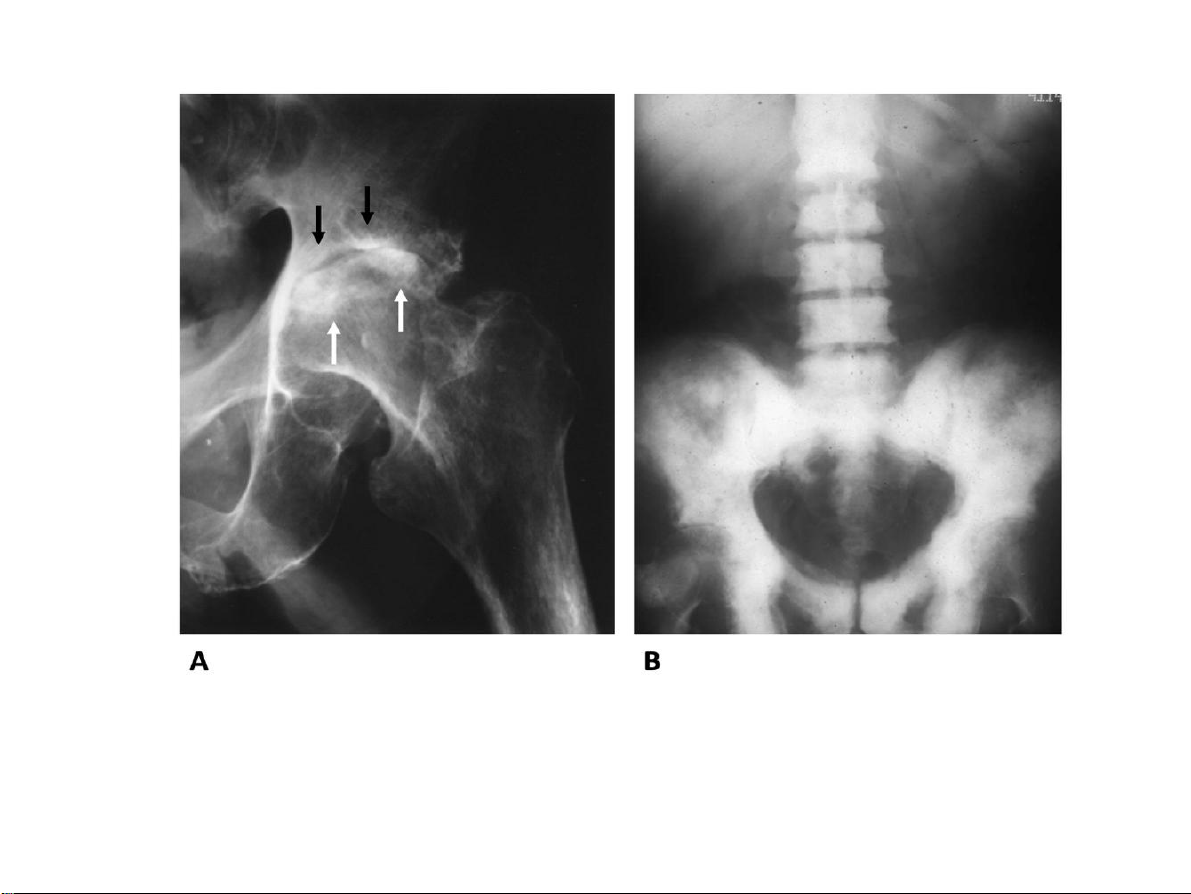

Hai ví dụ của quá trình tân tạo xương. Phản ứng đặc xương ở chỏm

xương đùi và mái ổ cối trong thoái hóa khớp háng (hình A). Đặc xương

lan toả ở cột sống thắt lưng, xương cùng và xương chậu hai bên trong di

căn xương từ ung thư tiền liệt tuyến (hình B). 31-Jan-23 CĐHA Cơ-Xương-Khớp